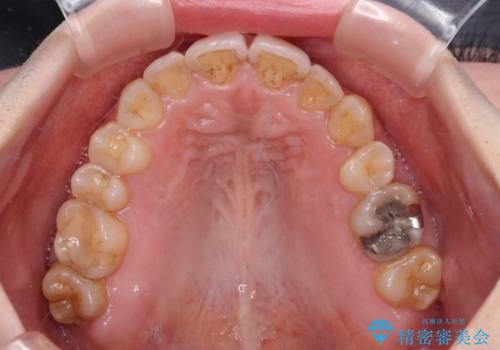

- 顕著な八重歯など、上下前歯のデコボコとスペースを気にして来院された患者様です。

八重歯改善には第一小臼歯の抜歯が必要であり、移動量が多いことから補助装置により八重歯を引き込むこととしました。

インビザラインでの治療をご希望であったので、インビザラインにて行うこととしましたが、右側前歯の改善にはワイヤー矯正が必要となる可能性があることをお伝えした上で治療を開始しました。

補助装置だけでなく、部分的にワイヤー矯正も使用しましたが、上下のスペースは改善しきれず、側切歯(前から2番目の歯)や顕著な八重歯は、インビザラインで治療するには限界があることがよく分かりました。

より良い仕上がりを希望される場合には、ワイヤー装置による矯正治療がお勧めとなります。